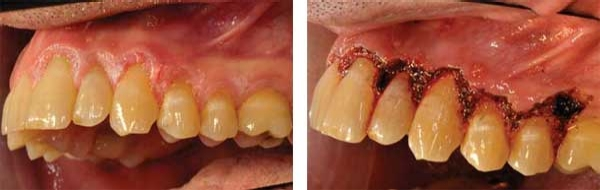

PVL of the gingiva has been suggested as a subset of proliferative verrucous leukoplakia (Fettig et al. 2009), targeting the specific tissue of the gingiva. Both the free and attached gingiva have been reported in these cases of PVL. Figures 3 and 4 depict a patient who was diagnosed with PVL (Figure 3) and suffered a recurrence of PVL (Figure 4) that was even more intense, with subsequent development of SCC.

Figure 1: Patient presents with clinical characteristics of PVL (courtesy of Dr. Thomas Caputo). Figure 2: Laser treatment of the affected area seen in Figure 1 (courtesy of Dr. Thomas Caputo). Figure 3: Proliferative verrucous leukoplakia before removal (courtesy of Dr. T.D. Rees). Figure 4: PVL after removal as seen in Figure 3. Recurrence with intense exophytic lesions during later diagnosis of SCC (courtesy of Dr. T.D. Rees).